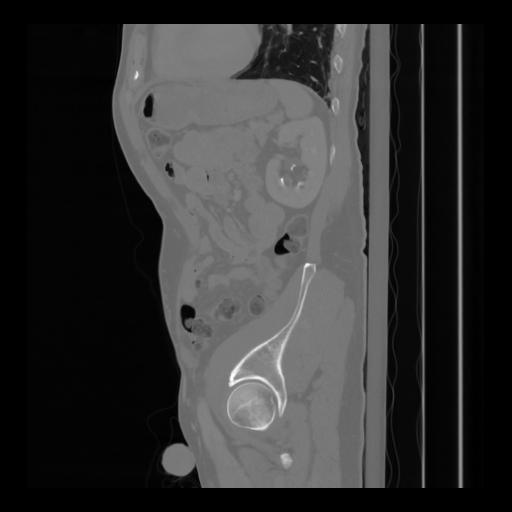

36 CUERPO,CE,Sagittal,3.000,CUERPO,Sagittal,